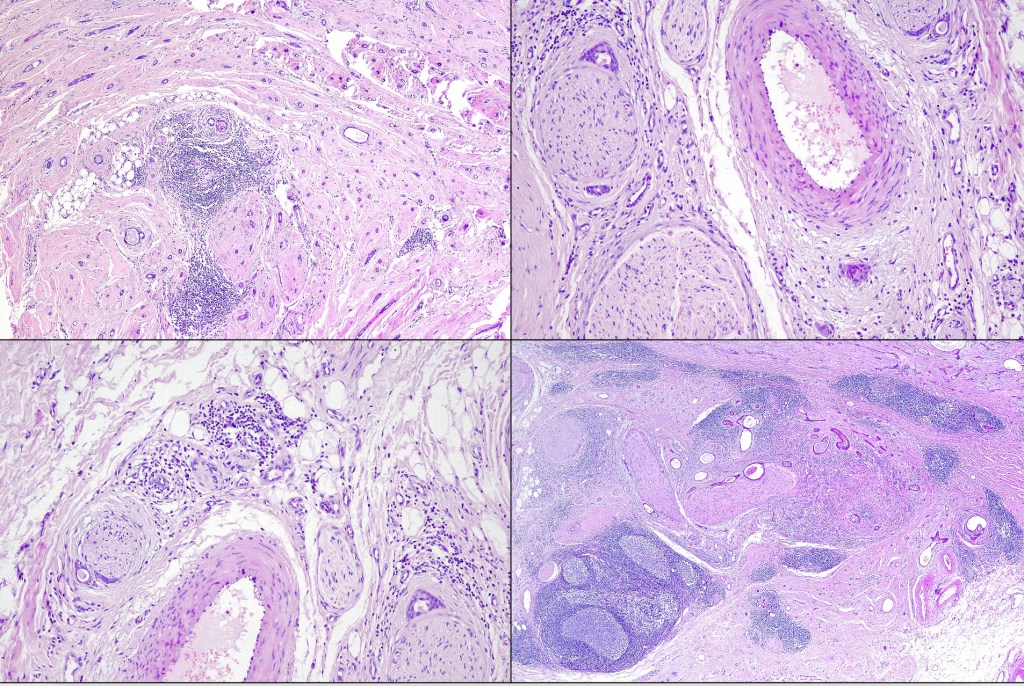

Histological features

•Hamartoma characterized by abnormalities of epidermis, hair follicles, sebaceous glands, apocrine sweat glands & connective tissue

•Follicular induction is common & sometimes trichoblastomatous foci are evident

•High, increased hyperplastic, sebaceous glands with openings onto the surface epithelium (in. old lesions, they may be absent)

•Reduced hair follicles

•Excessive numbers of apocrine glands

•May be complicated by a wide range of tumors (which are often multiple) including trichilemmoma, trichoblastoma, SCAP, sebaceous tumors, sweat gland tumors, melanocytic nevi & rarely by malignant tumors including BCC, SCC, melanoma, trichilemmal carcinoma, apocrine carcinoma & microcystic adnexal carcinoma